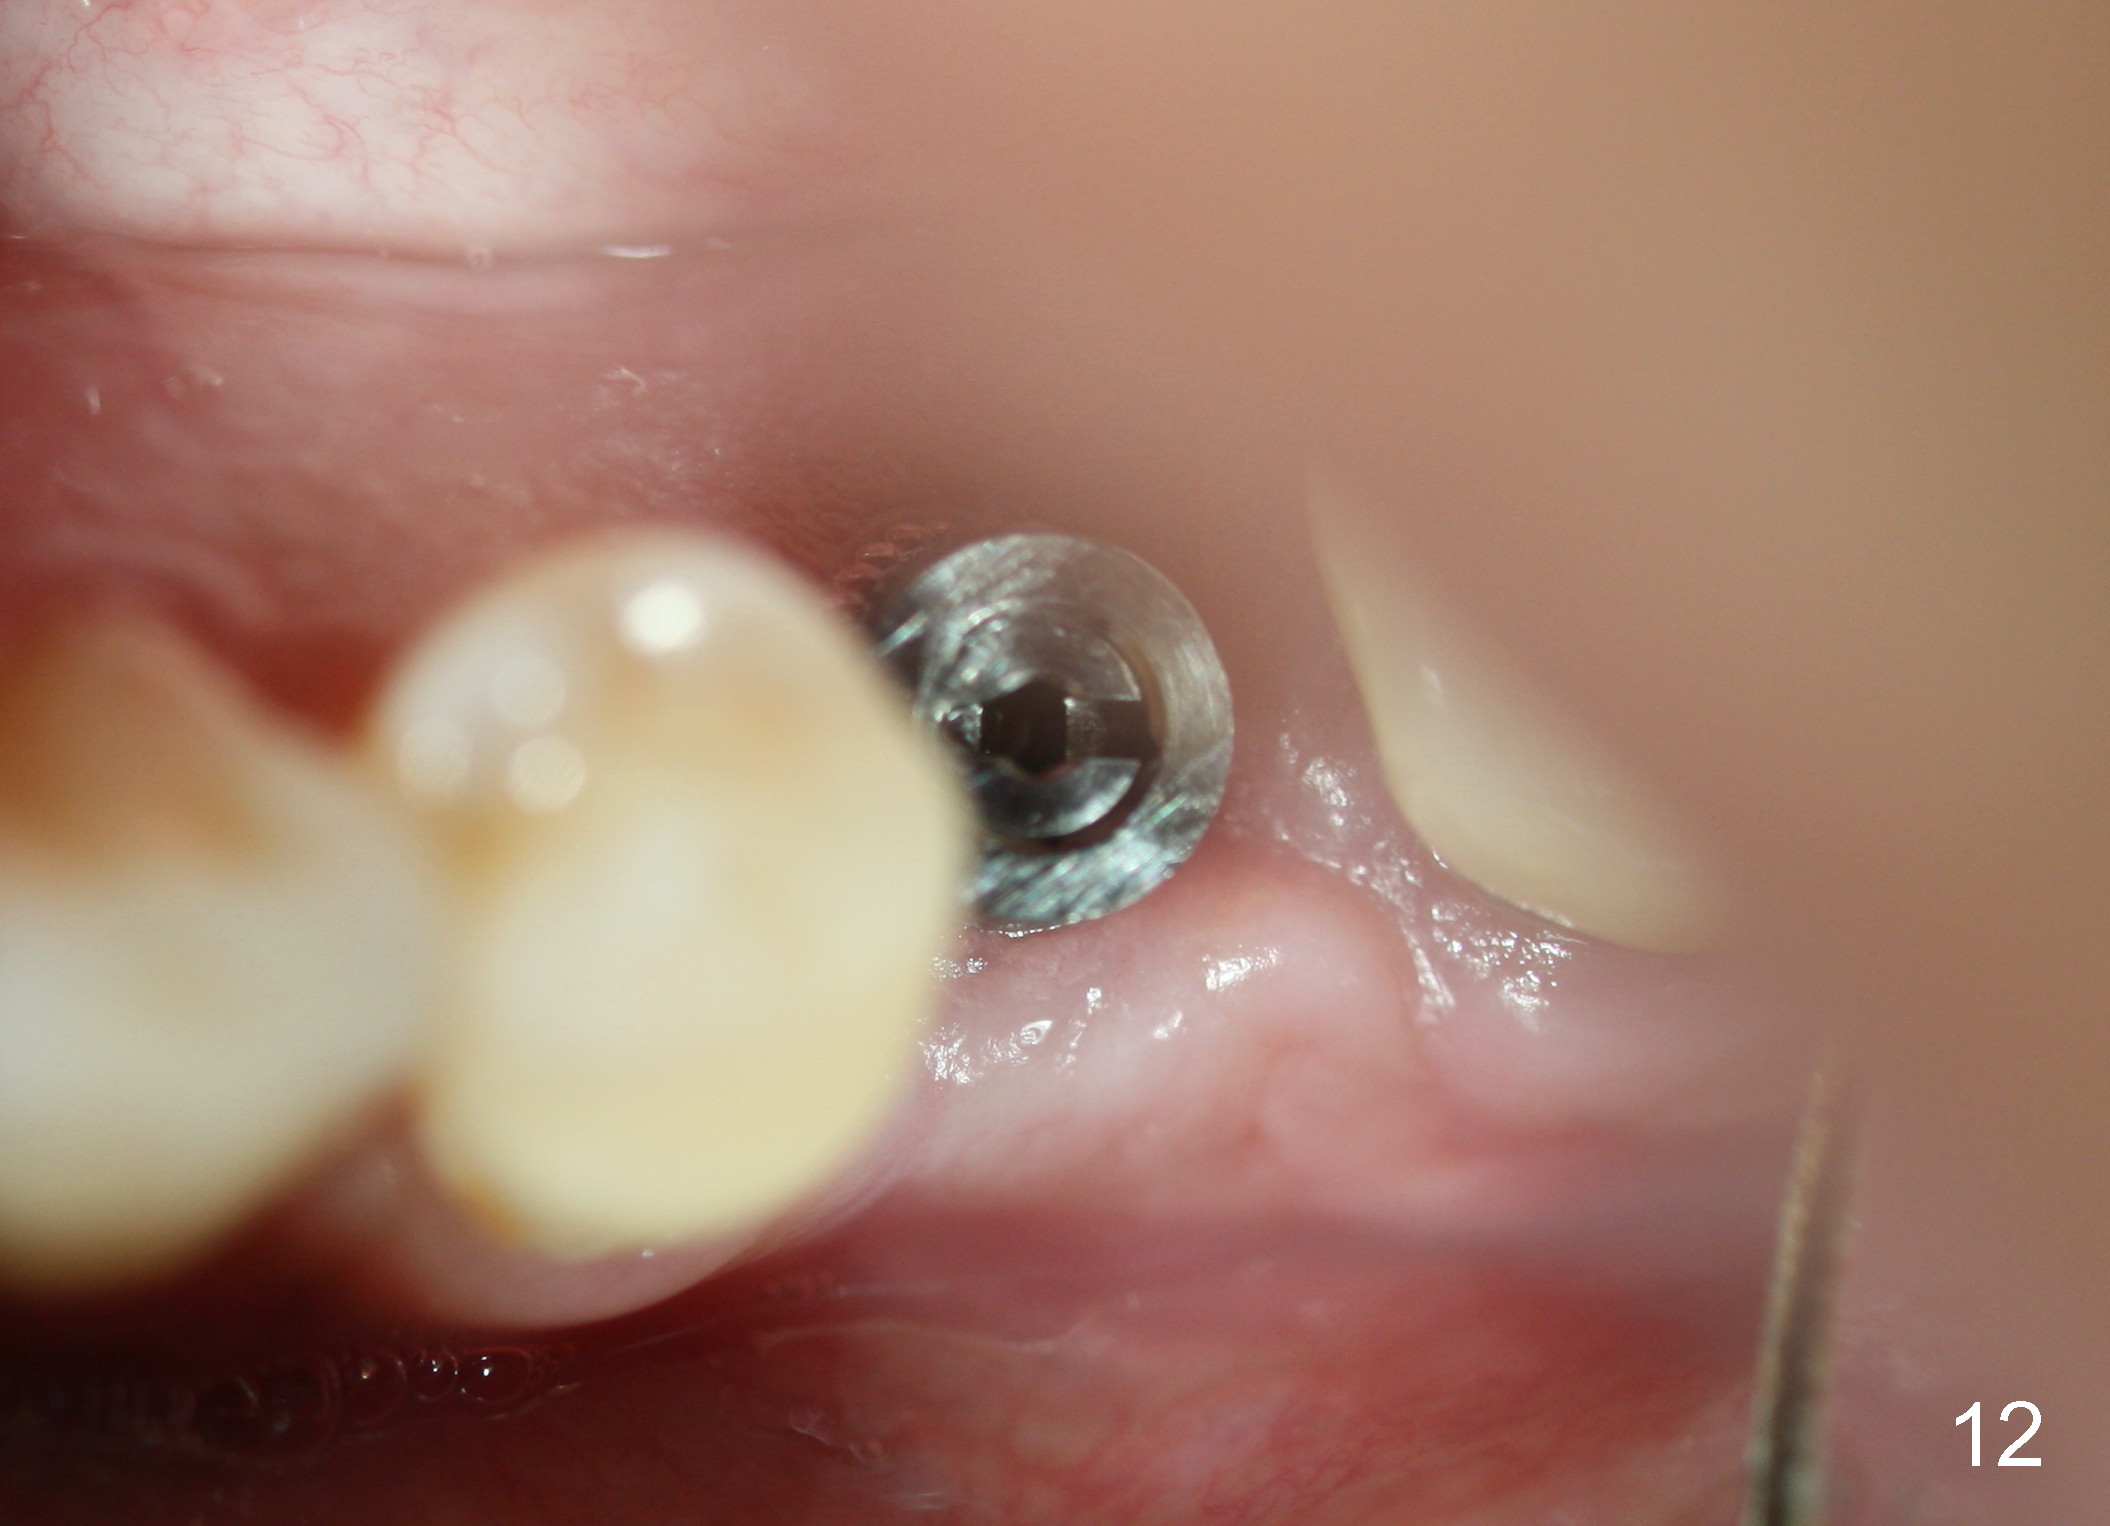

Twelve days post 2nd debridement, the wound does not heal normally. Out of desperation, Arestin is placed incompletely in the mesiobuccal pocket of #19. Fortunately, the wound heals at the site of #20 one month later (Fig.11). No infection is observed 4 months post 2nd debridement (Fig.12,13). Eventually the tooth #19 becomes symptomatic. Extraction and immediate implant is planned. In case the implant at the site of #20 fails, a cantilever bridge is fabricated using the posterior 2 implants.